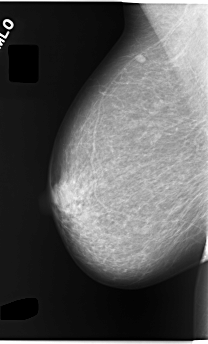

C_0055_1.RIGHT_MLO

RIGHT_CC LINES 5880 PIXELS_PER_LINE 3712 BITS_PER_PIXEL 12 RESOLUTION 50 NON_OVERLAY

RIGHT_MLO LINES 5848 PIXELS_PER_LINE 3528 BITS_PER_PIXEL 12 RESOLUTION 50 NON_OVERLAY